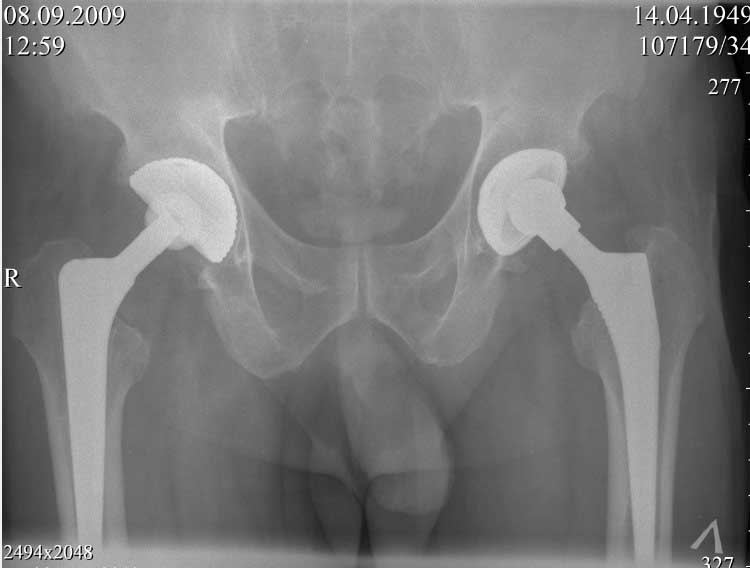

далее снимок в 2009 году